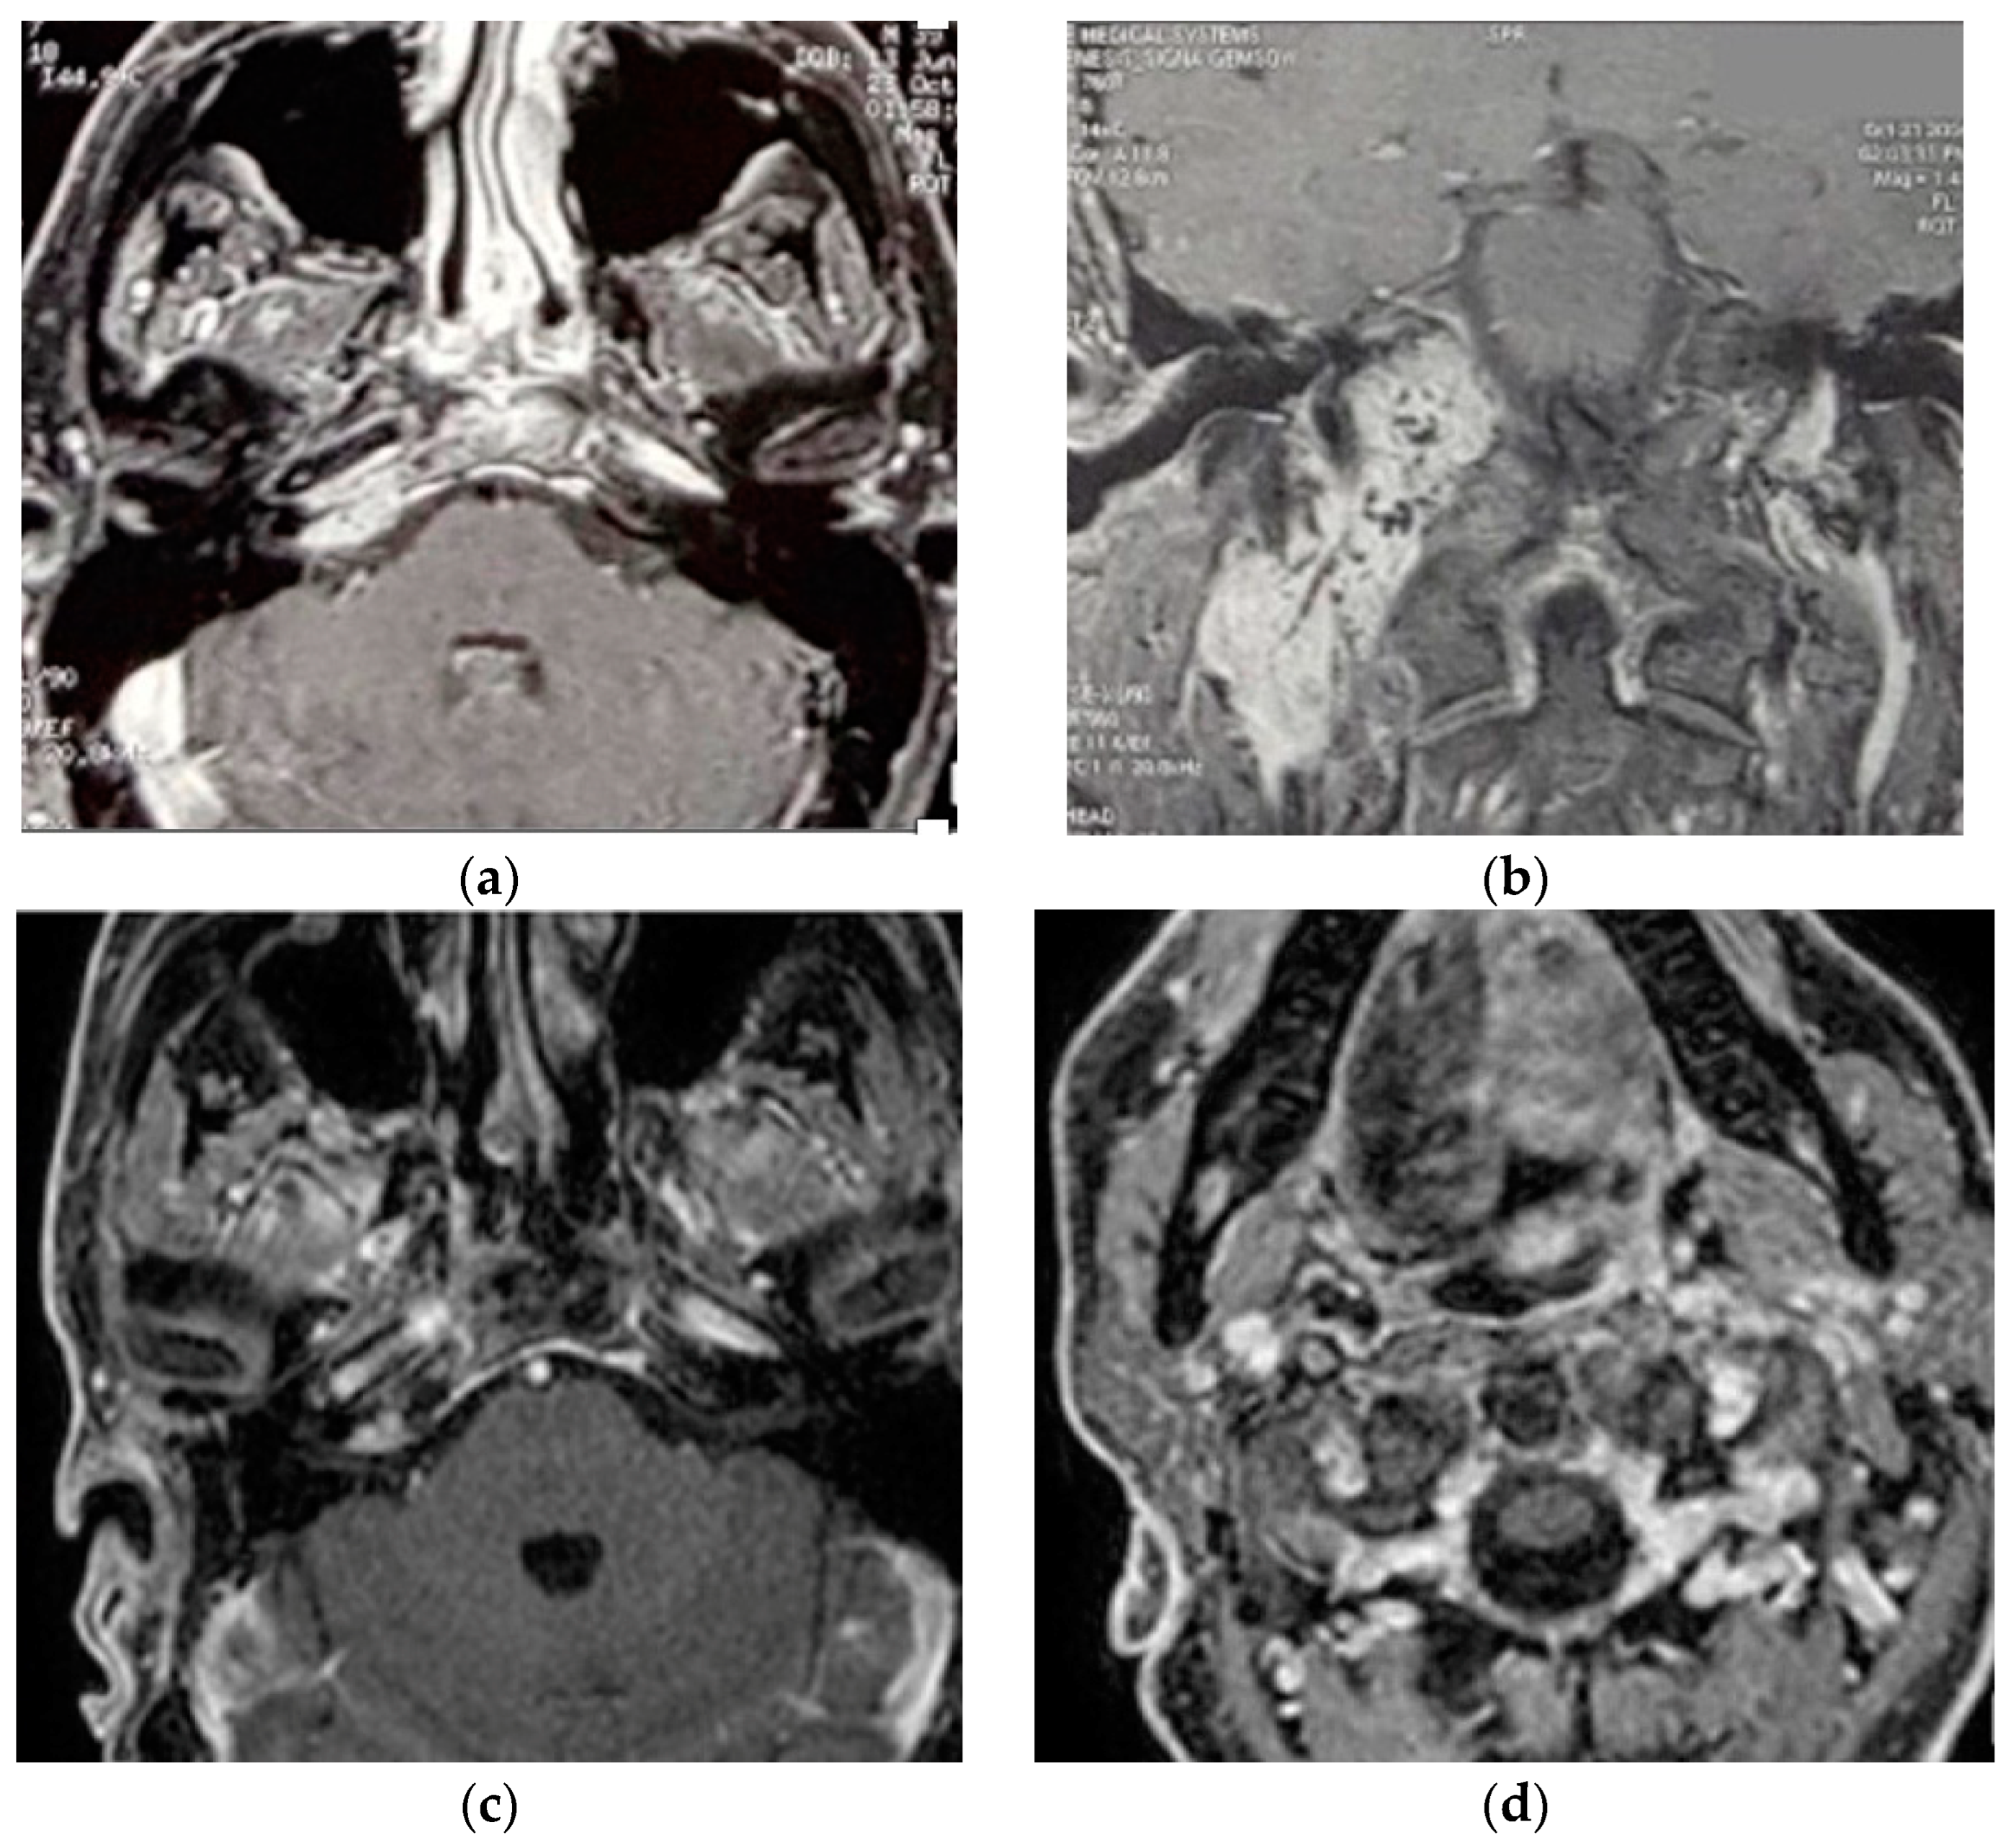

5.2. Case 2: (C3Di1 + Stage I VP)

5.3. Case 3: (C4Di2Vi)

5.4. Case 4: (C3Di2 + Stage II Vagal PGL)

5.5. Case 5: (C3Di2Vi)

5.6. Case 6: (C4Di2Vi)